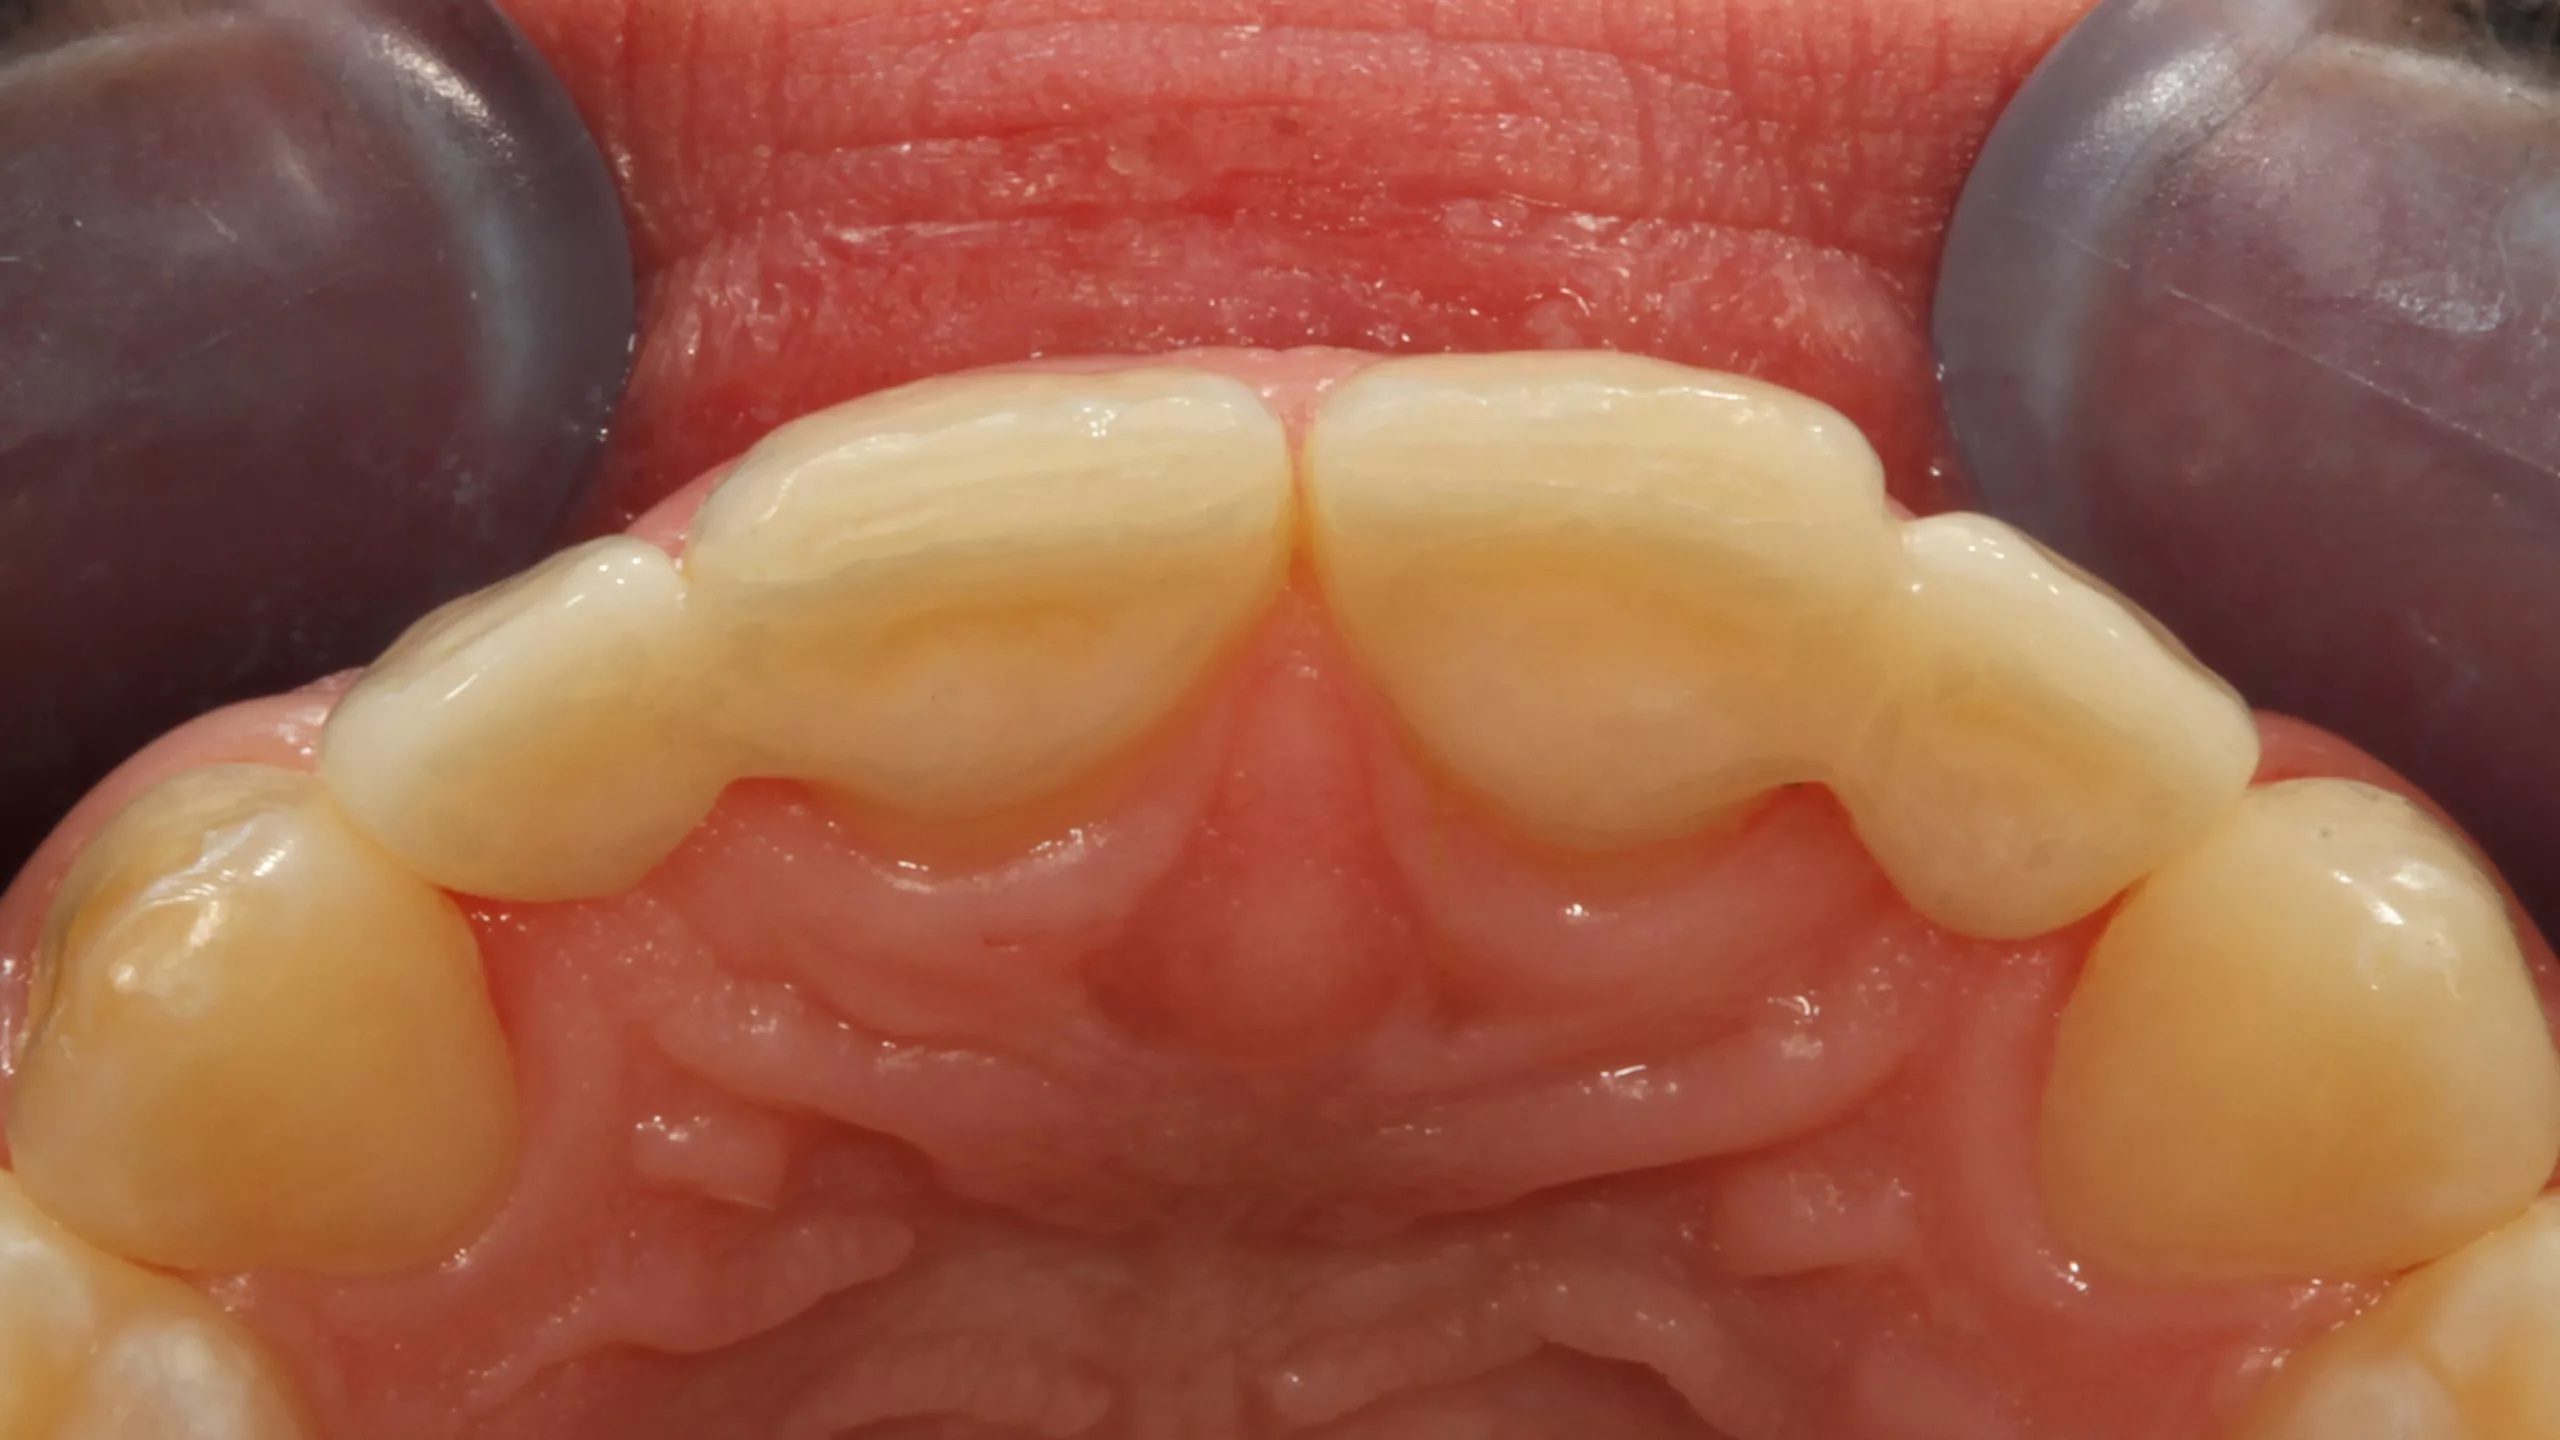

Die 32-jährige Patientin stellte sich mit einem komplett abgebrochenen, alio loco erstellten direkten Kompositaufbau an Zahn 22 vor (Abb. 10 und 11). Die beiden seitlichen Schneidezähne sind sehr kleine Zapfenzähne, deren ästhetische Verbreiterung vor einigen Jahren in direkter Technik vorgenommen worden war (Abb. 12). Aufgrund ihrer Press- und Knirschgewohnheiten mussten ihrer Angabe nach bereits mehrfach Ausbesserungsarbeiten vorgenommen werden. Die Vorpräparation ähnelte allerdings einer Veneerpräparation, sodass aufgrund der existierenden Vorpräparation und den erhöhten Anforderungen an die Stabilität im Beratungsgespräch eine indirekte Versorgungsform favorisiert wurde.

Direkte Frontzahnversorgungen mit Komposit funktionieren in der Regel hervorragend und sollten somit immer die 1. Wahl in der Überlegung alternativer Versorgungskonzepte darstellen. [6,31,37,55,58,59,62]. Es ist aber auch nicht zu unterschätzen, dass derartige Restaurationen sehr anspruchsvoll sein können [41,42]. Deswegen sind indirekte keramische Restaurationen – meist aus Glaskeramik – eine valide Alternative, wenn höchste ästhetische Ansprüche befriedigt werden müssen. [3,4,7,20,34, 40,43,44,57,65,89,98]. Ergibt allerdings eine Vorpräparation eine Ausgangssituation, die präparationstechnisch kaum verändert werden muss, und müssen erhöhte Anforderungen an die Bruchfestigkeit gestellt werden, ist eine indirekte Restauration die 1. Wahl, da keine weitere invasive Präparation erforderlich und eine bessere Langzeitprognose gegeben ist. So fiel die Entscheidung zugunsten einer labial verblendeten monolithischen Vollzirkonkrone (Abb. 13 und 14). Es wurde erwogen, Zahn 12, der mit einem vergleichbaren Kompositaufbau versorgt worden war, wie Zahn 22 mitzuversorgen. Da an dem Zahn 12 aber kein Akutereignis Berücksichtigung finden musste, verzichtete die Patientin auf diese zusätzliche Behandlungsoption. Bei der Formgestaltung wurde in Absprache mit der Patientin bewusst keine Rücksicht auf die jetzige Form von Zahn 12 genommen und eine symmetrische Versorgung bewusst ignoriert, um bei einer Neuversorgung von Zahn 12 in der Zukunft dann keine Formkompromisse eingehen zu müssen. Die Form der neugestalten seitlichen Schneidezahnkrone orientierte sich somit ausschließlich an den Zähnen 21 und 23 und den gegebenen vertikalen Dimensionen.